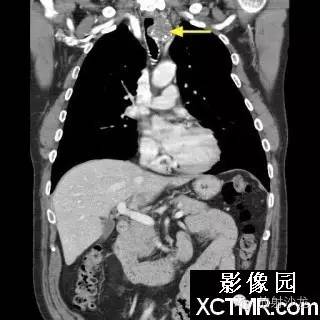

On the contrast-enhanced CT of the chest, there is a heterogeneous mass arising from the left lateral wall of the trachea. The mass demonstrates extratracheal extension as well as extension into the tracheal lumen. (Figure 1 and Figure 2). The mass also contains internal calcifications (arrows), representing chondroid matrix mineralization (Figure 3 and Figure 4).

胸部增强扫描示气管左侧壁发出一不均质的肿块影,肿块向气管内外扩展(图1、2)。其内可见钙化影(箭头),代表软骨基质的钙化(图3、4)。